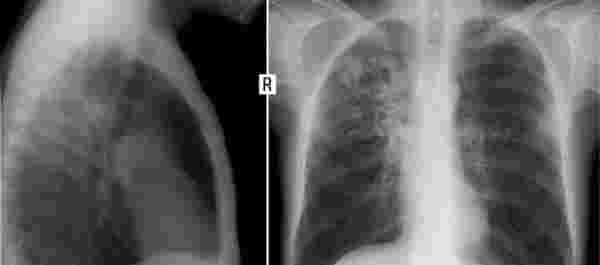

當這些固體顆粒物進入肺部后能完全堵塞肺泡,從而影響肺部的擴張,像上文的王大爺,本來就有肺結節,如果繼續吸茶煙,那么結節會越來越大,加快肺癌的進程。